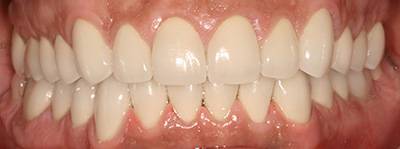

11. eset

27 éves páciensünk egész életében rettegett a fogorvosi beavatkozásoktól. Az összes foga elszuvasodott. A legkárosodottabb fogak gyökérkezelése és a szuvasodásainak megszűntetése után 26 fémkerámia koronát kapott a páciens. Erre a kezelésre is nagyon büszkék vagyunk. 2 hét leforgása alatt sikerült jelentős mértékben javítanunk a páciensünk mosolyán, önbizalmán és mióta velünk talalákozott, már a fogászati kezelésektől sem fél annyira!